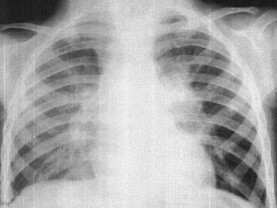

111、单项选择题

女,3岁,低热、咳嗽2月余,结合胸片,最可能的诊断为()

A.原发综合征

B.肺门淋巴结核

C.淋巴瘤

D.支原体肺炎

E.间质性肺炎